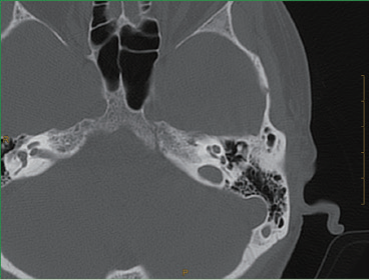

Толщина изображений томографии точности только 0.275mm, и структуры внутреннего уха как

ossicles и улиткаа, и отношение между структурами внутреннего уха ясно видимы, как

соединение malleus и incudis сборников.

Обычное томографическое изображение внутреннего уха